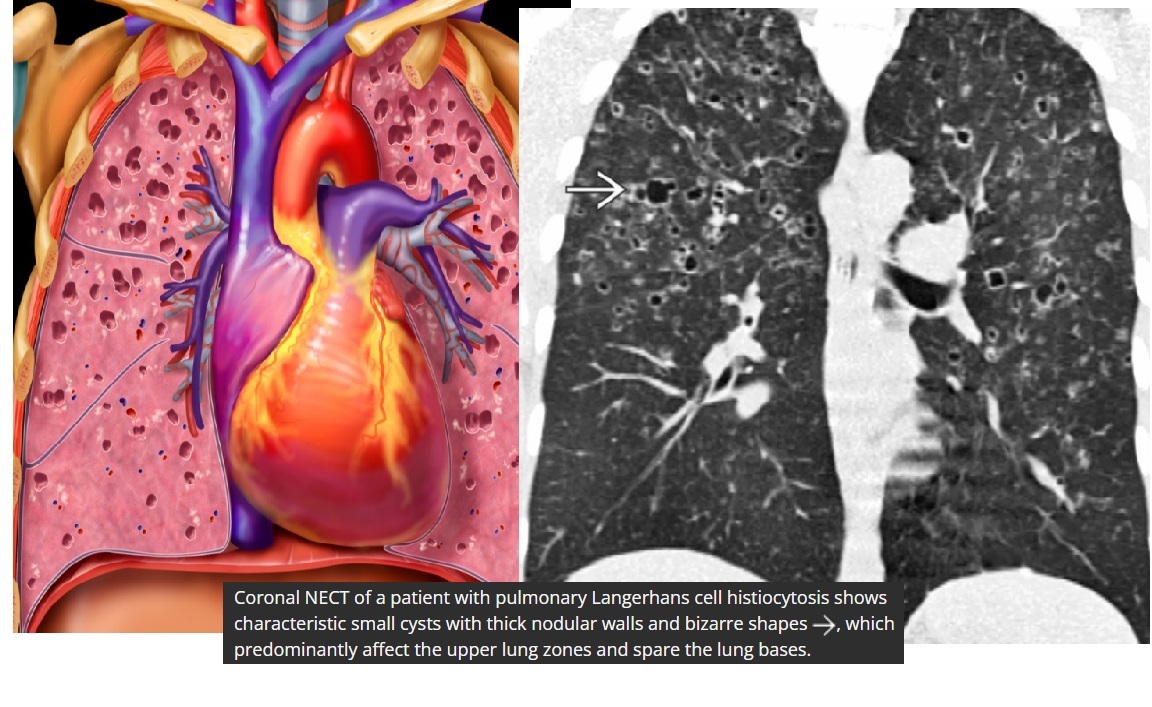

Pulmonary Langerhans cell histiocytosis (PLCH)

Predominant upper lobes

bizarre-shaped thick pulmonary cysts

Smokers

Early stages of disease, 1-10mm nodules in mid/upper zone predominant

Effusions are rare

Sparing costophrenic angles